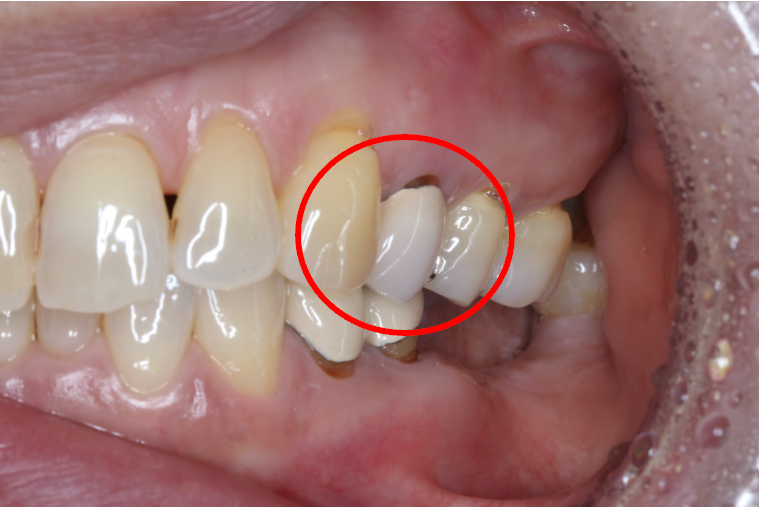

セラミック症例②

年齢 40代女性

治療期間 1ヶ月

治療内容 ジルコニア

治療箇所 右上6番

治療費用 100,000円